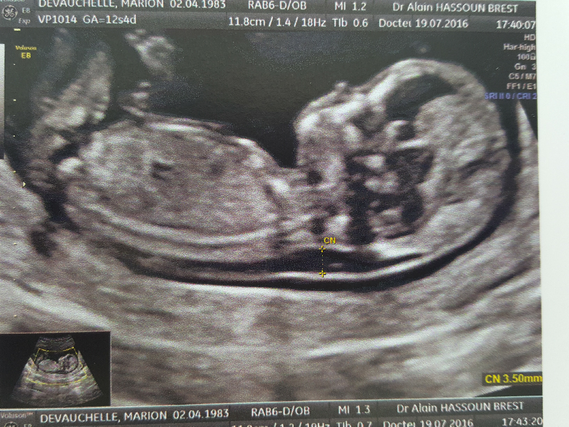

Clarté nucale 4 mm clarté nucale a 42mm Amniocentèse FORUM Grossesse 1ere echo 11 sa et 3 jrs, clarté nucale 42 mm!

La mesure de l'épaisseur de la clarté nucale permet de déterminer un risque d'anomalie chromosomique chez le fœtus trisomie 21, mais aussi trisomie 13 et 18 " Plus cette épaisseur est augmentée, plus le risque que le bébé soit trisomique est augmenté ", informe le radiologue " Une clarté nucale épaisse avec un caryotype normal Voilà, vendredi dernier je passe ma T1 et le gynéco nous annonce une clarté nucale anormale et plutôt épaisse (3,11mm), il m'oriente donc sur la pds tri test dès l'aprèsmidi Le médecin m'appelle lundi pour me donner les résultats très mauvais, je suis dans les cas à risques très élevés (1/14)